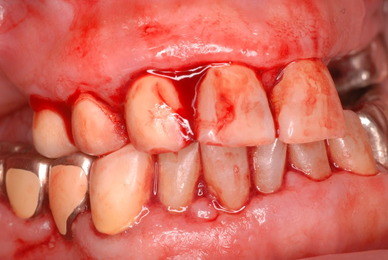

歯周病の疑いで東京のかなり遠方の方が来院されました。

驚くべきことですが、定期検診は受けていたそうです。しかしながら歯周病の指摘は受けたことがないそうです。

何故か?定期検診が虫歯のチェックのみになり、又肝心の歯周病の検査や歯周病の部分の予防や治療のためのブラシの使い方などを学んだ事がないのです。

本当に患者さんのことを考えると憂鬱になります。歯周病が悪化すると殆ど回復は無理だからです。